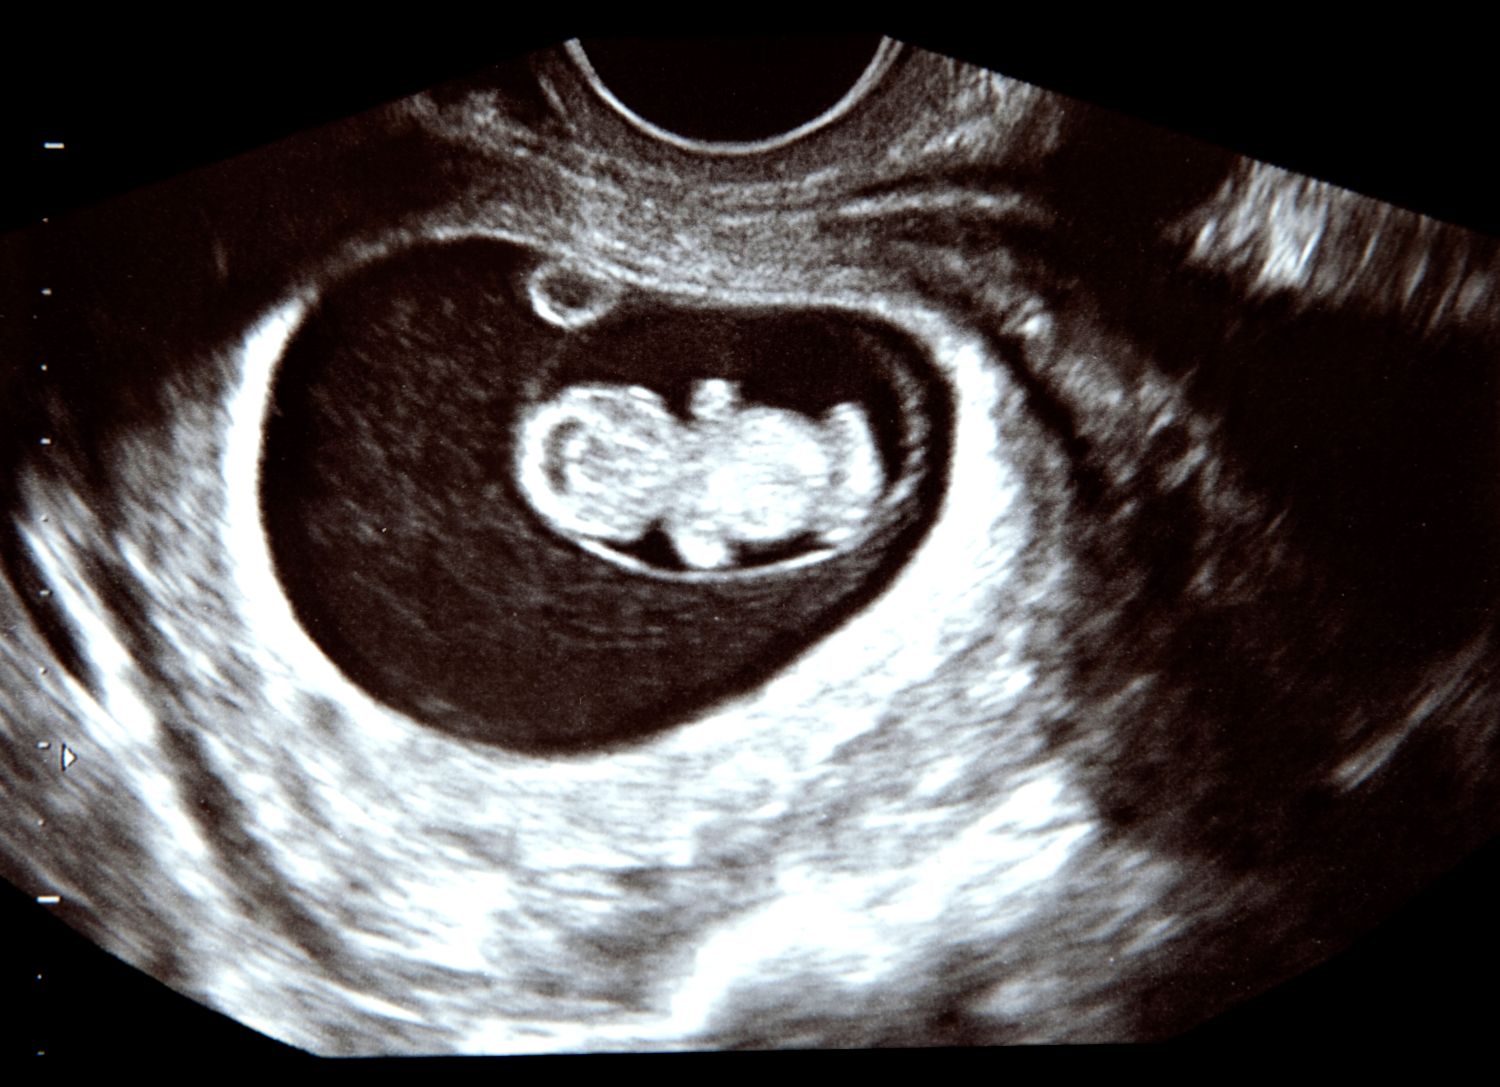

УЗИ 10 недель беременности

Эмбрион на 10 неделе беременности УЗИ

УЗИ 10 недель беременности

УЗИ 10 недель беременности